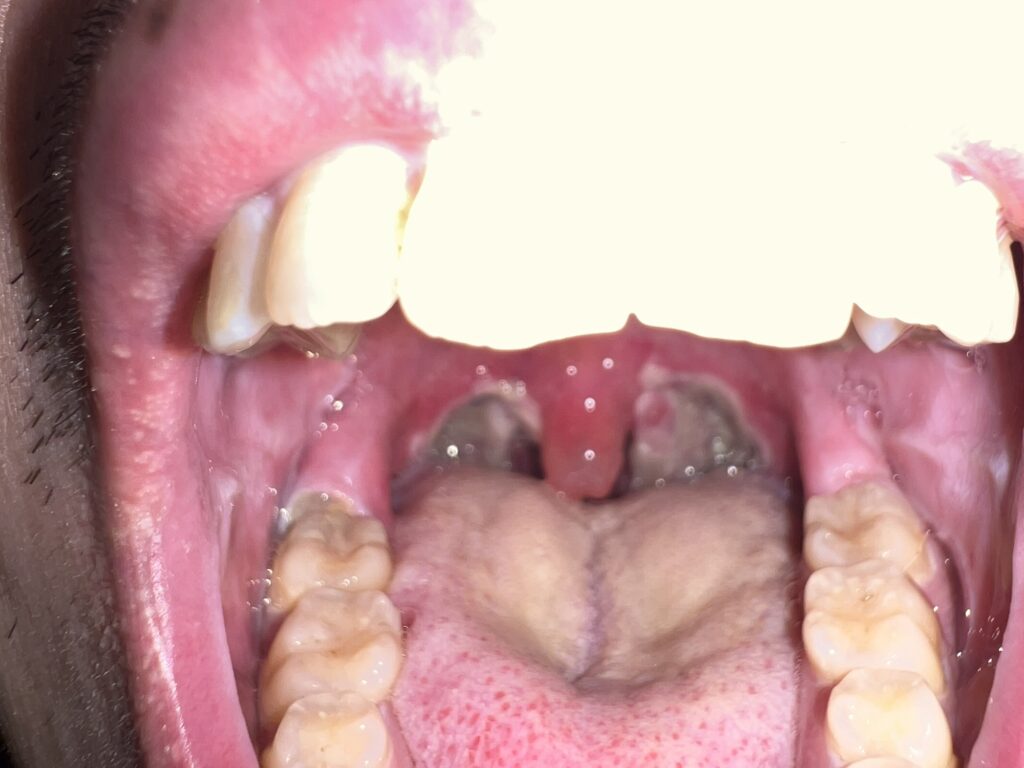

11月19日(手術翌日)

舌の奥で感じられるガサガサ感…これがカサブタなのかなと。未だに痰がエンドレス過ぎて座って寝てます( •᷄ὤ•᷅)

11月20日

手術箇所がどんどん白くなってカサブタが多くなって来てますねぇ